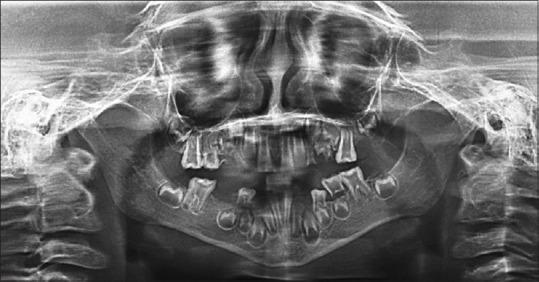

Dentinogenesis imperfecta type II: Diagnosis, functional and esthetic rehabilitation in mixed dentition.

Full Mouth Rehabilitation of Two Siblings with Dentinogenesis Imperfecta Type II Using Different Treatment Modalities.

Dentinogenesis imperfecta: long-term rehabilitation in a child.

Dentinogenesis imperfecta type II: A case report with 17 years of follow-up.

A multidisciplinary approach to the functional and esthetic rehabilitation of dentinogenesis imperfecta type II: A clinical report.